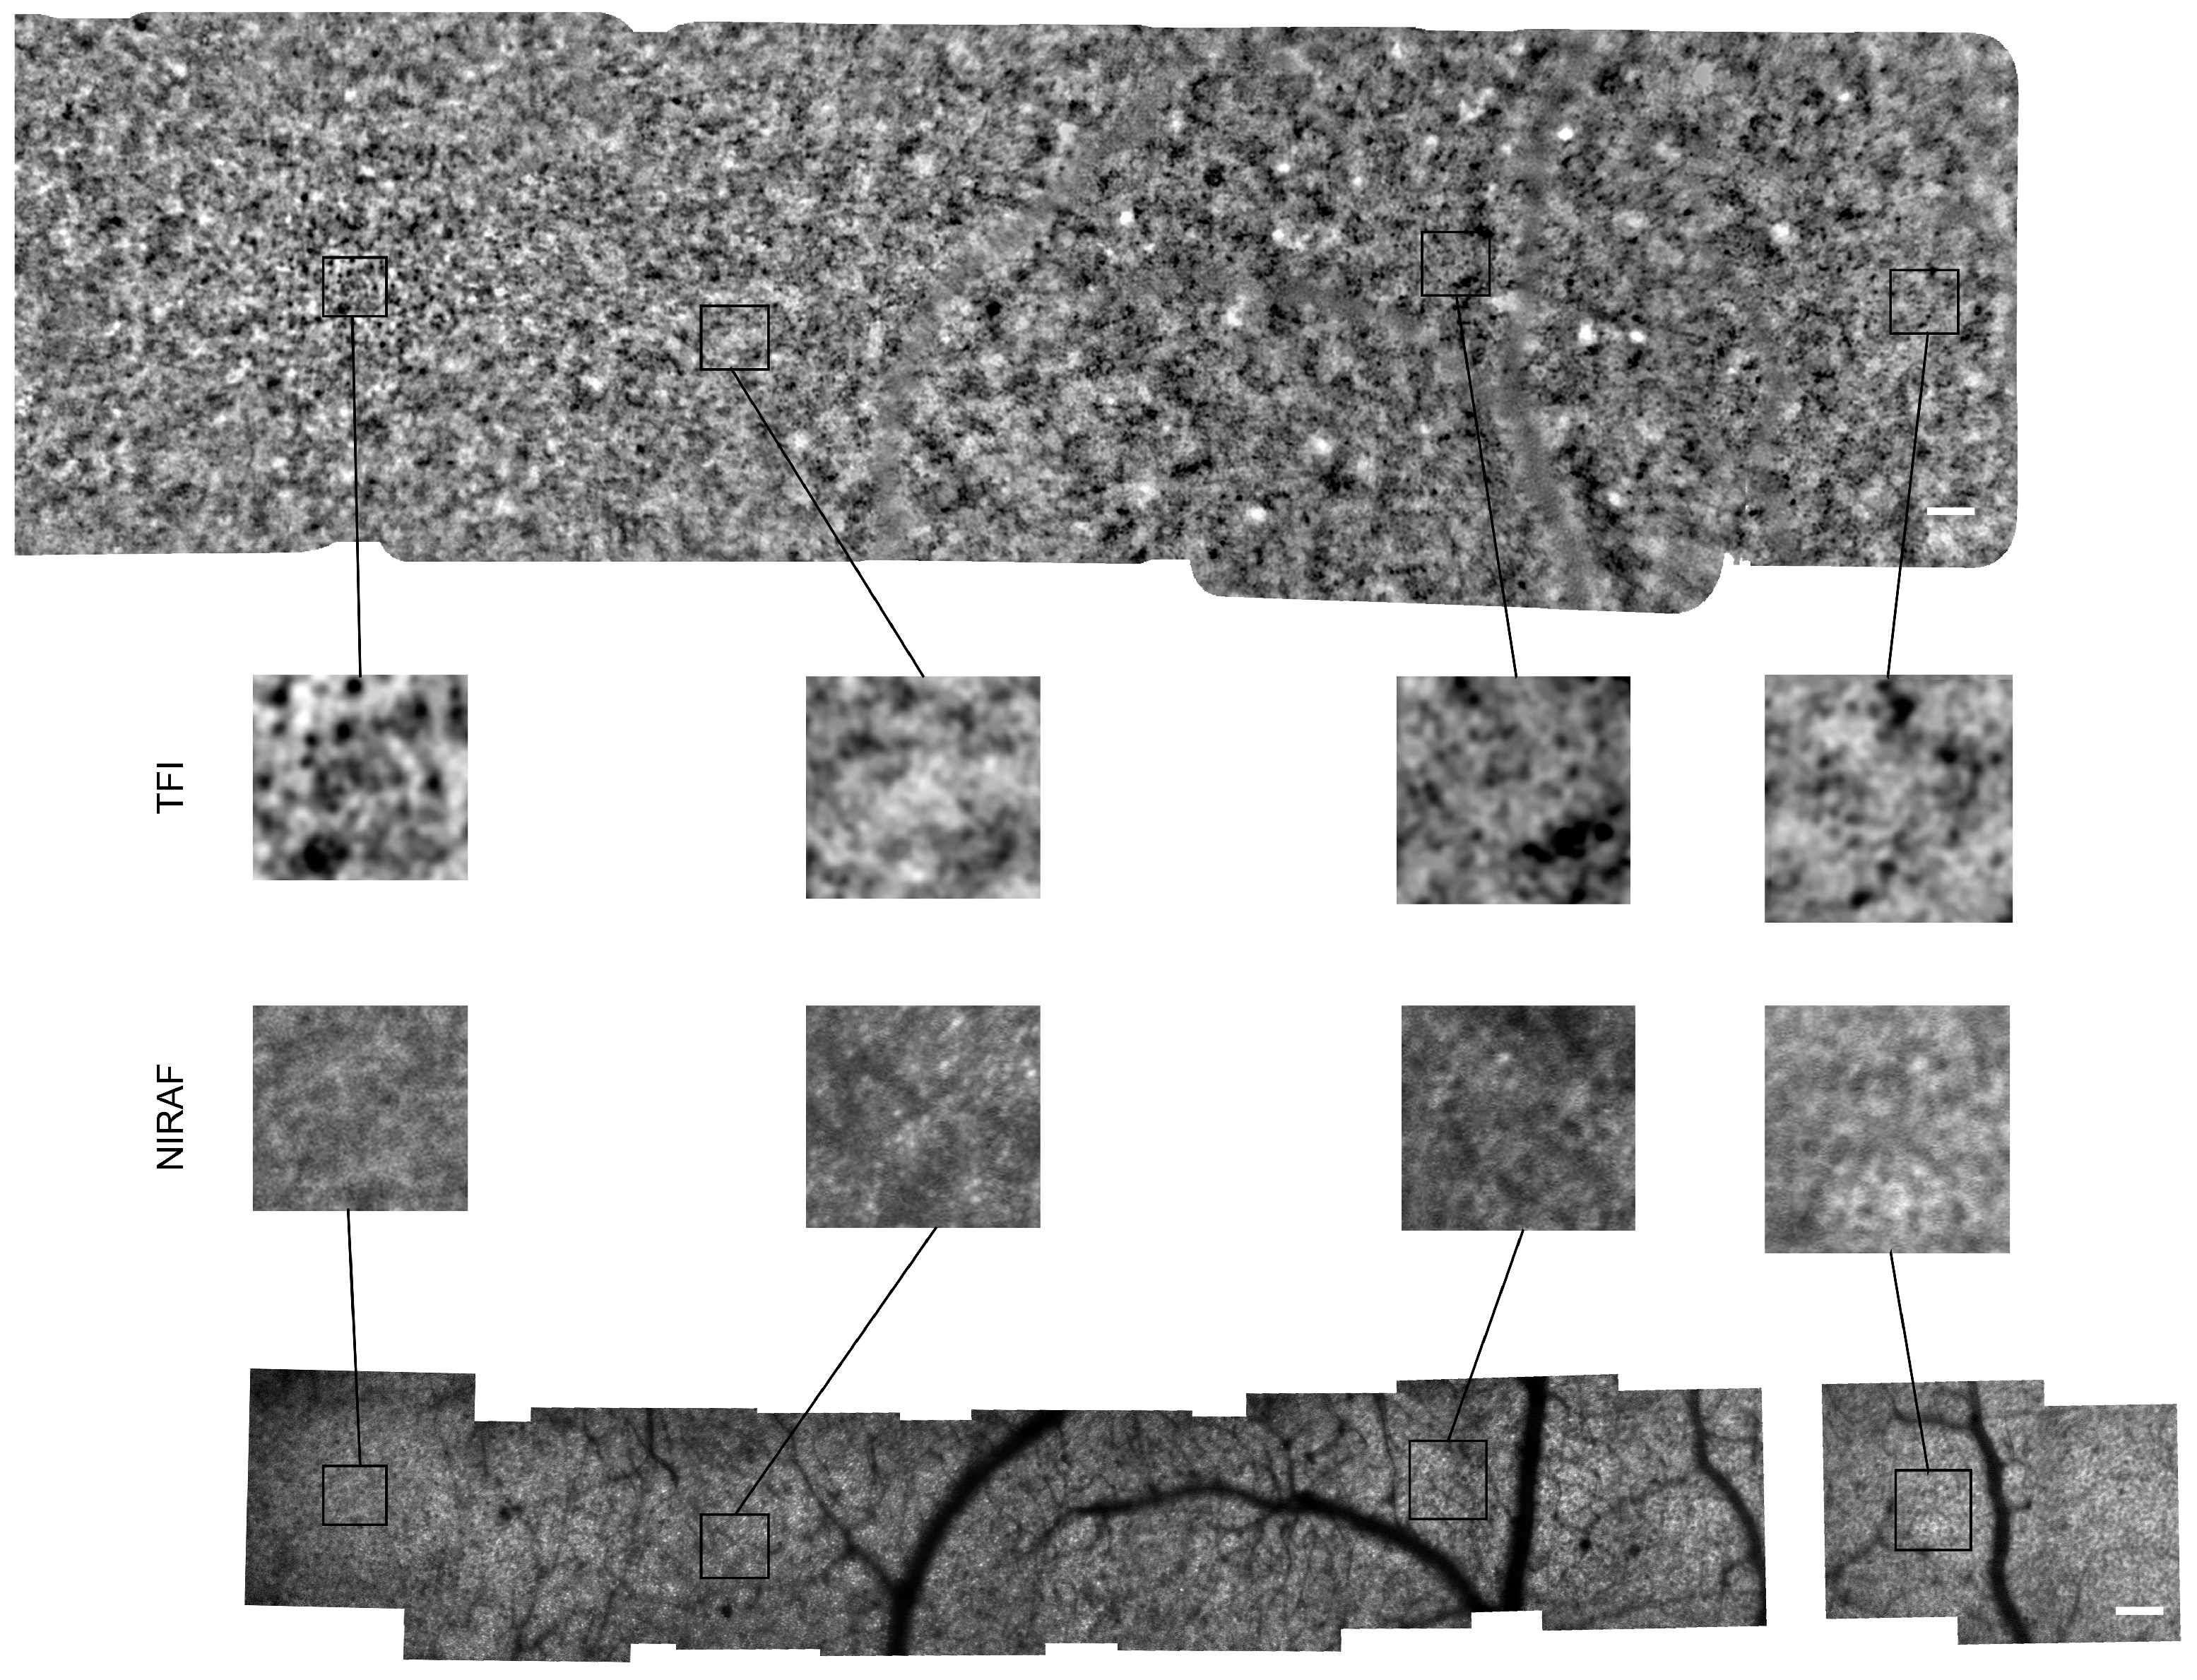

3.1. Images of TFI and NIRAF of Same Regions

Appendix A. Montages of TFI and NIRAF Images from Other Subjects

Appendix A.1. Montages of Subject #2

Appendix A.2. Montages of Subject #3